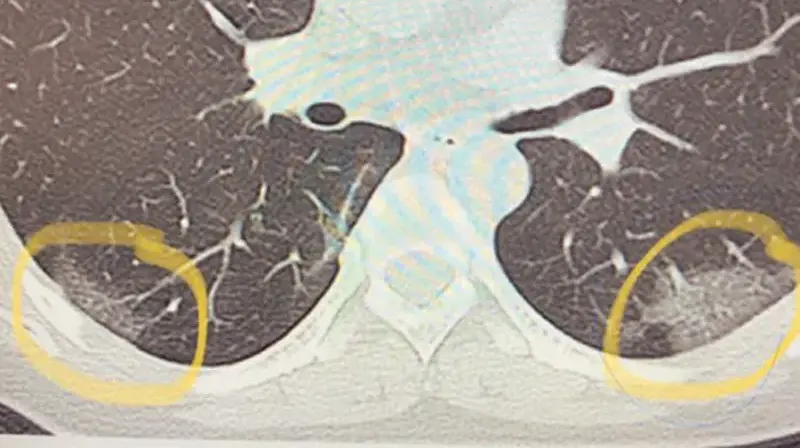

Breast Cancer Screening: Thermogram No Substitute for Mammogram

August 2020

Dr. Cyrus Khorrami, MD

Dense Breasts: What Does this Mean?

October 2015